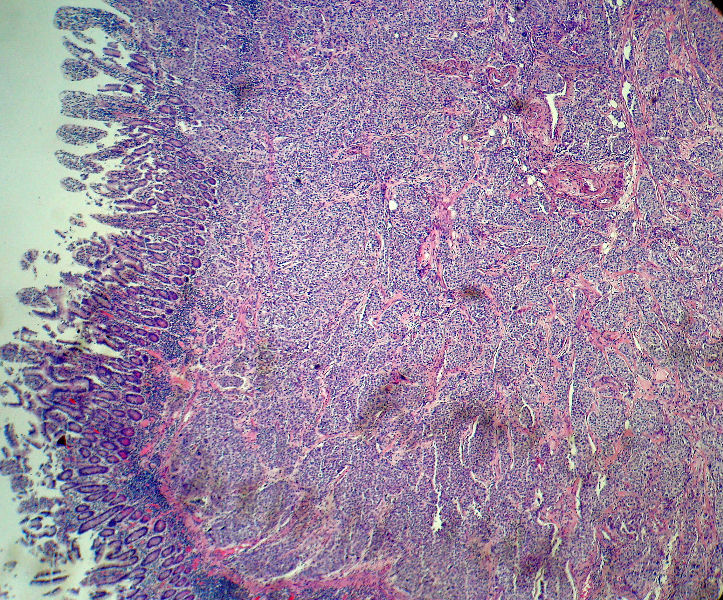

男,82岁,小肠穿孔紧急手术。

大体,小肠一段,长约60厘米,与粘膜面可见三个溃疡型肿物,肠系膜淋巴结肿大。

肿瘤呈巢片状分布,细胞大小相对一致,胞浆丰富,胞核呈细颗粒状,可见小核仁,血管较丰富,考虑神经内分泌肿瘤,加做免疫组化(Ki67、Syn、NSE、CgA、CD56)分级。

肠系膜淋巴结

神经内分泌肿瘤,加做免疫组化(CKp、Ki67、Syn、NSE、CgA、CD56)分级。